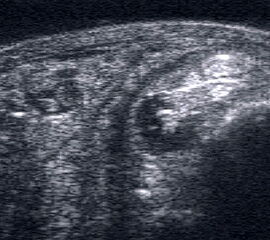

Dorsaler TS hinter dem Innenknöchel.

Abbildung 46

Lagerung: Rückenlage, Außendrehung des Beines.

Schnittführung: TS und LS hinter dem Innenknöchel beginnen und bis zum Os cuneiforme mediale fortführen.

Referenzstrukturen: Innenknöchel, Talus, Os naviculare, Os cuneiforme mediale, Sehnen der Mm tibialis posterior, flexor hallucis longus, flexor digitorum.

Befunde: Häufig betreffen die Pathologen die Tibialis-posterior-Sehne, die als erste Sehne hinter dem Innenknöchel zur Darstellung kommt. Halo-Phänomen und echoarme Verdickung bei akuter Tendinopathie, zunehmend inhomogen und echogen mit Kaliberschwankungen bis hin zu Teilrupturen bei Chronifizierung 5. Für die Erkennung von Teilrupturen sind TS in verschiedener Höhe besonders wichtig. Bei komplettem Riss mit Retraktion im LS Bild wie Spargelspitze mit umgebender Flüssigkeit oder Hämatom. Ein Os tibiale externum erscheint als echoreiche Struktur im Verlauf der Tibialis posterior Sehne mit dorsaler Schallauslöschung. Ein Os naviculare cornutum imponiert als starke Prominenz im Ansatzbereich der Tibialis posterior Sehne.